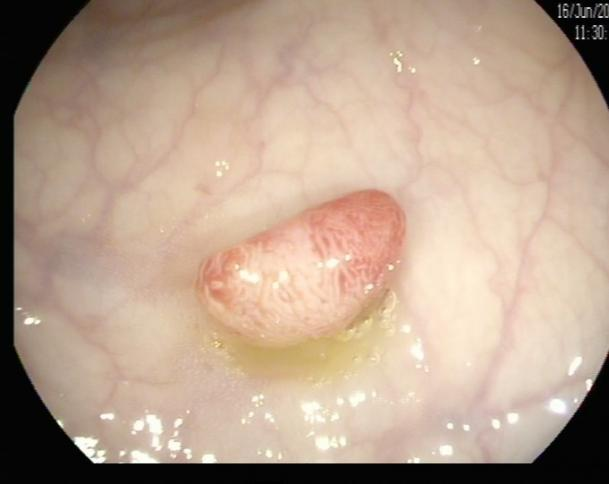

(2)陈先生(44岁,乙状结肠息肉,图2)

肠镜一照,息肉现形!形态各异的大肠息肉,离癌有多远?(图2)

图2

病理诊断:(乙状结肠)管状腺瘤,局灶癌变-黏膜内癌(腺癌),脉管未见癌栓,蒂未见累及。

解读:这是从腺瘤发展成癌的典型案例。“局灶癌变”指息肉中只有一小部分区域发生了真正的癌变。“黏膜内癌”指癌细胞仍局限于黏膜层内,尚未穿透黏膜肌层向更深层浸润。脉管无癌栓、蒂部未累及是非常积极的信号,表明癌细胞尚未通过血管/淋巴管扩散,也未侵犯息肉蒂部。此时完整切除息肉,很大可能达到根治效果。距离进展期癌:非常近,但尚属极早期,原位癌/粘膜内癌。